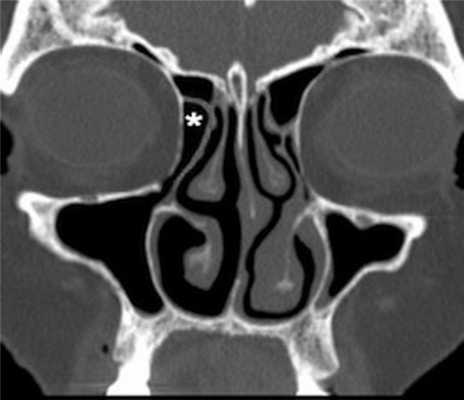

(Слева) На сагиттальной КЛКТ (реконструкций) визуализируется большое куполообразное объемное образование без кортикальной пластинки с плотностью мягких тканей (гиперденсное относительно воздуха), сопоставимое с муцинозной ретенционной псевдокистой верхнечелюстной пазухи. Край пазухи возле кисты интактен.

(Справа) На аксиальной КЛКТ (реконструкция) визуализируется муцинозная ретенционная псевдокиста, занимающая всю камеру правой верхнечелюстной пазухи на этом уровне. Важно не спутать перегородку в пазухе с кортикальной пластинкой на периферии образования. Обратите внимание на утолщение слизистой оболочки камер левой верхнечелюстной пазухи.